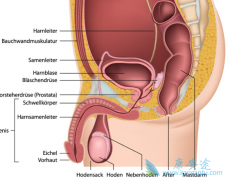

���� غ�谩 ��һ�ֶ�����������������ֳϵͳ����ļ�������Լռ���Զ���������2%��20~40��������׳������غ�谩����Ϊ�������Ը߷��İ�֢֮һ��غ�谩�ķ���ԭ��Ϊ������֪���� ������������غ�谩֢״����Щ��1��غ���״��״����״�������ȣ��� ...

����غ�谩���ڶ���������һ�֣������Ļ���ҲԽ��Խ�࣬�Ӷ�Խ��Խ�ܵ����ǵ����ӣ�Ϊ���ܹ����õķ������Ʒ������DZ���� غ�谩֢״ �����˽⣬����������������ǰ������ϣ��������õ����á� ����غ�谩������ʲô���֣�1������غ����ʹ���г�һ�գ� ...

����غ���������˵�Ǻ���Ҫ�����٣�غ�費�����ˣ��㱾���߱������Լ��ؾͲ��������ˡ���������Ҫע���Լ���غ�轡����20�������������ģ�����Ҳ��Ҫ��������Ͳ���������غ�谩�ķ������ʾ���20��45��֮�䡣�����֢״����������Ҫ�ġ�����һ��Ҫ�˽� ...